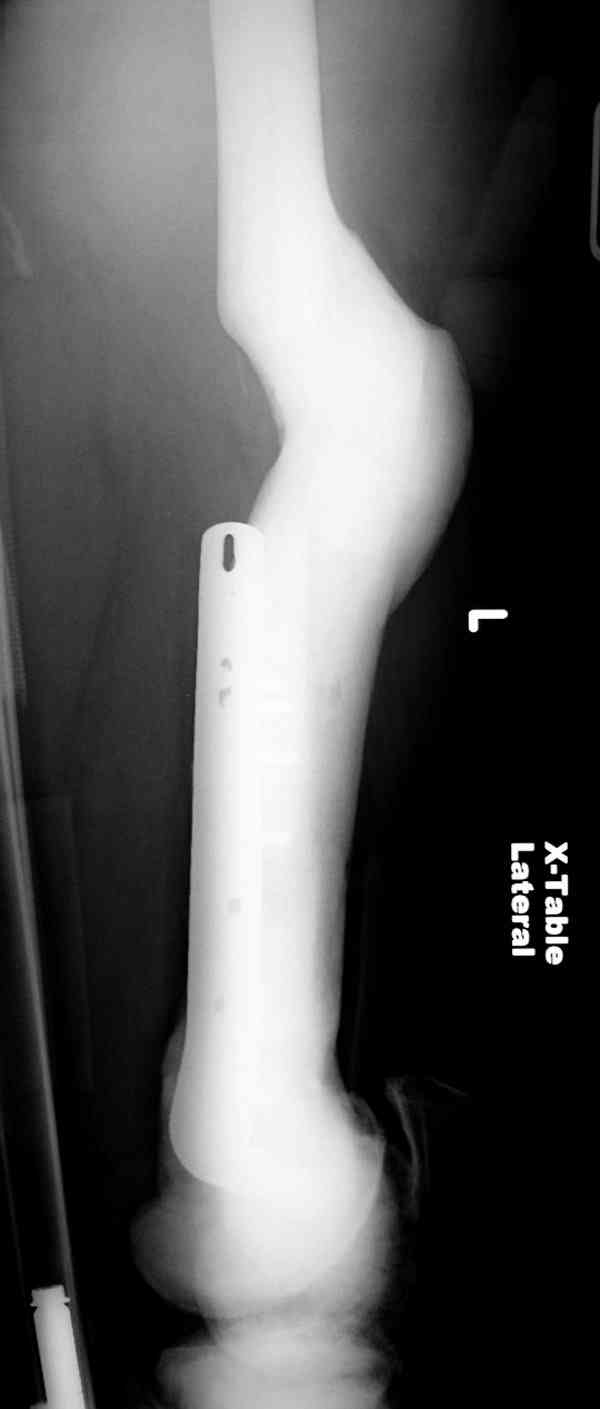

После неудачной попытки скелетного вытяжения в первом мед.учреждении, после осмотра снимков и изучения истории, поставили диагноз “Остеопетроз” или мраморная болезнь, редкая наследственная костная паталогия, где имеется нарушение формации остеокластов.

Конечно, было бы идеальным применение интрамедуллярного остеосинтеза, но учитывая прежний собственный опыт (лечил перелом бедра) и

публикации, предупреждающие о трудностях при обработке кости (иногда из-за неподготовленности инструментария результатом была неадекватная фиксация перелома, или перенос операции из-за фактора усталости оперирующего персонала), решили применить пластину (и в этом же случае был выбран Synthes plate, так что представитель за два дня

зароботал... на десерт тоже).

Заказаны были дополнительные различные дрели, и на следующий день, усиленной бригадой, больного прооперировали, потратив на каждое отверстие около 25-35 минут, хотя сверлили с охлаждением по нарастающей по диаметру сверл и с их заменой каждые 2 мм сверления.

Теперь стоит задача со сращением перелома, из-за отсутствия литературных данных по применению костных стимуляторов при остеопетрозе, и не зная как поведет в этой среде Grafton, все таки надеюсь, что даст толчок к стимуляцию, решил применить пастообразную деминерализованную костную матрицу, расположив спереди между отломками.